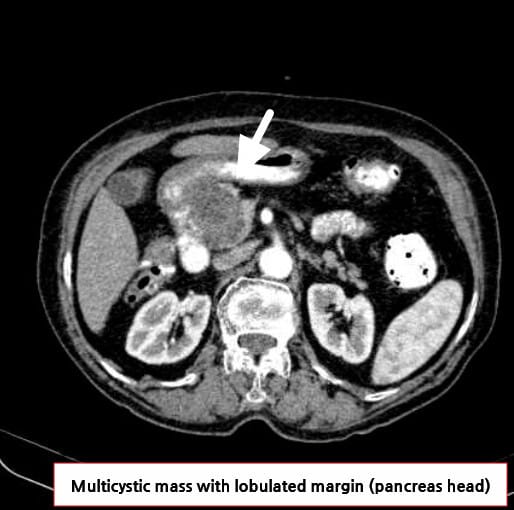

대부분 무증상이며, 췌장 전반 어디서나 발생할 수 있지만 특히 췌두부에서 잘 발견됩니다. 낭종 내 중심성 흉(central scar)이 특징입니다.

영상검사에서 중심성 흉을 동반한 벌집 모양 낭종 소견이 특징적이며, 대부분 비침습적으로 진단 가능합니다.

| 벌집 모양(microcystic), 중심성 흉과 석회화, 균일한 장액 음영을 확인합니다. |

영상 소견

벌집 모양(microcystic) 낭종, Central scar, 석회화 등

| 🟦 Microcystic pattern |

| 수 mm 크기의 다수의 낭종이 집합된 형태입니다. |

| 🟦 Central scar with calcification |

| 중심에 석회화를 포함한 반흔이 특징적으로 관찰됩니다. |

Niknejad M, Pancreatic serous cystadenoma. Case study, Radiopaedia.org (Accessed on 18 Jul 2025) https://doi.org/10.53347/rID-85866